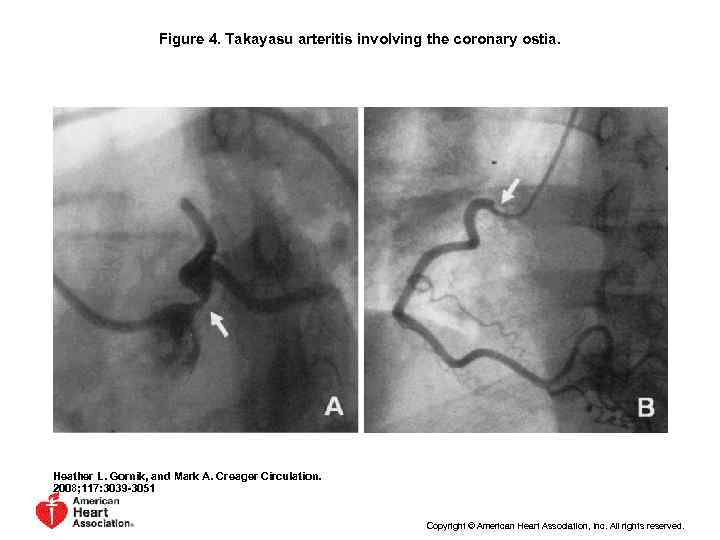

Coronary involvement in TA • Occurs in 10~ 30% • Often fatal • Classified into 3 types Type 1: stenosis or occlusion of coronary ostia Type 2: diffuse or focal coronary arteritis Type 3: coronary aneurysm

Figure 4. Takayasu arteritis involving the coronary ostia. Heather L. Gornik, and Mark A. Creager Circulation. 2008; 117: 3039 -3051 Copyright © American Heart Association, Inc. All rights reserved.